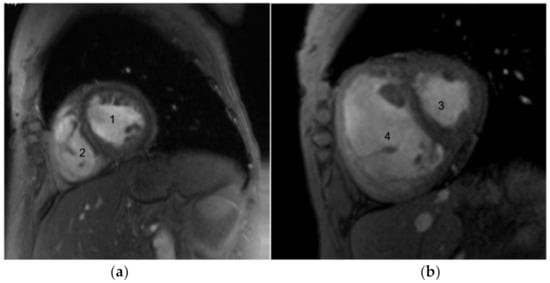

4.5. Cardiac MRI

- Bezante, G.P.; Rollando, D.; Sessarego, M.; Panico, N.; Setti, M.; Filaci, G.; Molinari, G.; Balbi, M.; Cutolo, M.; Barsotti, A.; et al. Cardiac magnetic resonance imaging detects subclinical right ventricular impairment in systemic sclerosis. J. Rheumatol. 2007, 34, 2431–2437. [Google Scholar]

- Hachulla, A.-L.; Launay, D.; Gaxotte, V.; De Groote, P.; Lamblin, N.; Devos, P.; Hatron, P.-Y.; Beregi, J.-P.; Hachulla, E. Cardiac magnetic resonance imaging in systemic sclerosis: A cross-sectional observational study of 52 patients. Ann. Rheum. Dis. 2008, 68, 1878–1884. [Google Scholar] [CrossRef]

- Hagger, D.; Condliffe, R.; Woodhouse, N.; Elliot, C.A.; Armstrong, I.J.; Davies, C.; Hill, C.; Akil, M.; Wild, J.M.; Kiely, D.G. Ventricular mass index correlates with pulmonary artery pressure and predicts survival in suspected systemic sclerosis-associated pulmonary arterial hypertension. Rheumatology 2009, 48, 1137–1142. [Google Scholar] [CrossRef]